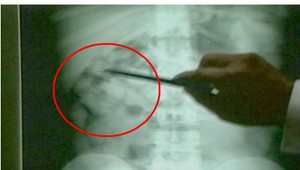

Mladík si najskôr našiel na internete lieky s vysokým obsahom psychotropných látok, potom sa mu podarilo vyrobiť takýto - takmer dokonalý recept - na meno svojej starej mamy. Z internetu tiež odkopíroval pečiatky dvoch lekárov a s falošnými receptami sa vybral do lekárne.

Tieto lieky sú určené najmä pre onkologických pacientov, ktorí trpia silnými bolesťami. Jeden z liekov patrí medzi najsilnejšie omamné látky a je vlastne náhradou morfínu. Mladík ich chcel ale pravdepodobne predať drogovo závislým. Podľa lekárničky sú jeho účinky porovnateľné s účinkami heroínu. Vedúca lekárne Eva Kulichová vysvetľuje: "Vyhľadávajú ho najmä tí zdraví ľudia, ktorí sú návykovo závislí na omamných látkach, pretože je silno halucinogénny."